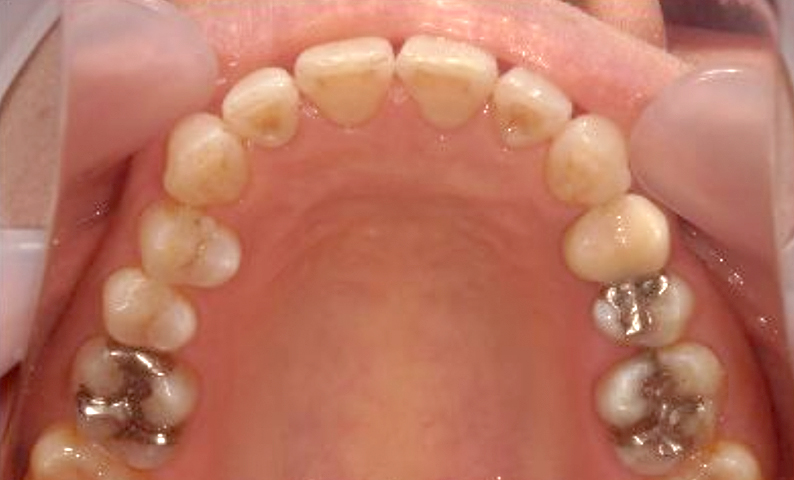

症例_003 上顎だけの部分矯正

治療期間:9ヶ月金額:30万円+税女性前歯のガタガタ八重歯上の前歯だけ

| Before | After |

|---|---|

|